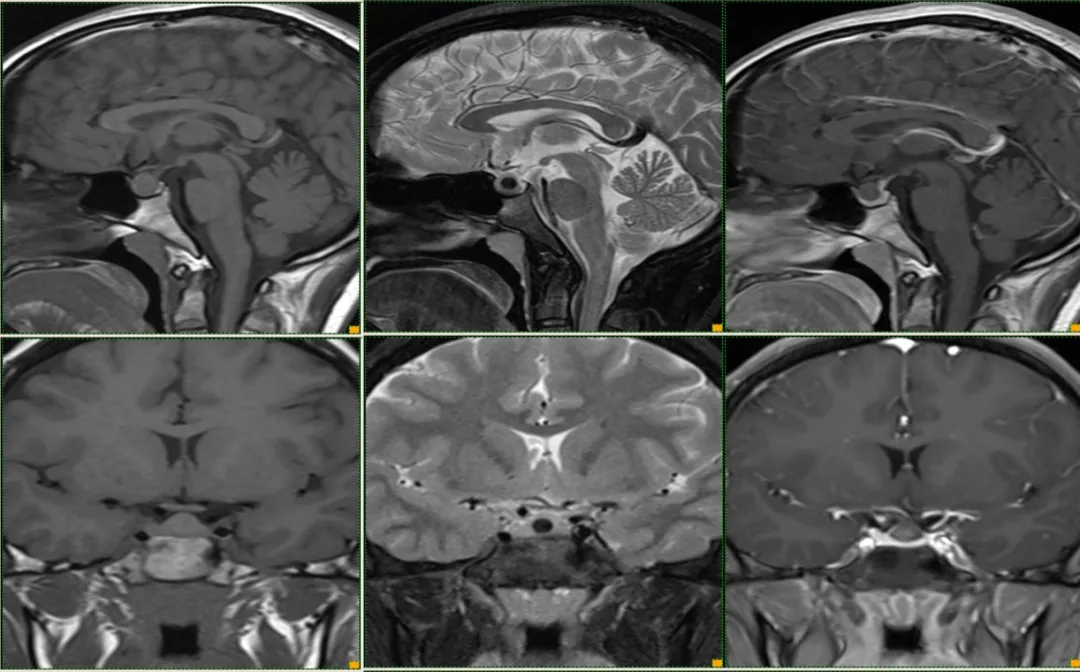

case 15:一年半前偶然发现,无明显症状,怀疑垂体瘤卒中,服用过一段时间溴隐亭,后经北京天坛医院诊断 Rathke 囊肿后后停药,现复查较前片无变化。

形态信号异常,与垂体瘤卒中难以鉴别,但与患者既往检查片比较无异常改变,遂考虑囊肿可能

T1WI 高信号症状性 RCC 与出血性垂体瘤卒中鉴别:

• 冠状面对称、体积较小、信号均匀、增强边界光滑清晰、囊内结节提示→RCC。

• 体积大,冠状面不对称、信号不均匀、增强边界毛糙、鞍旁结构受侵、分隔征、液液平面征则提示→垂体瘤卒中。

case 16:男,38y ,偶然发现

延迟强化,垂体微腺瘤

case 17:f/59y

强化高峰出现较正常垂体腺晚,在团注造影剂后 3 min 内为最佳时间。强化持续时间长,必要时延迟扫描,延迟期肿瘤较垂体腺显著强化,信号高于正常垂体腺。动态强化很有必要。

小结:先天发育异常。多位于鞍内、形态多规则、MRI 信号多样,特征性表现—囊内小结节,囊肿本身无强化。